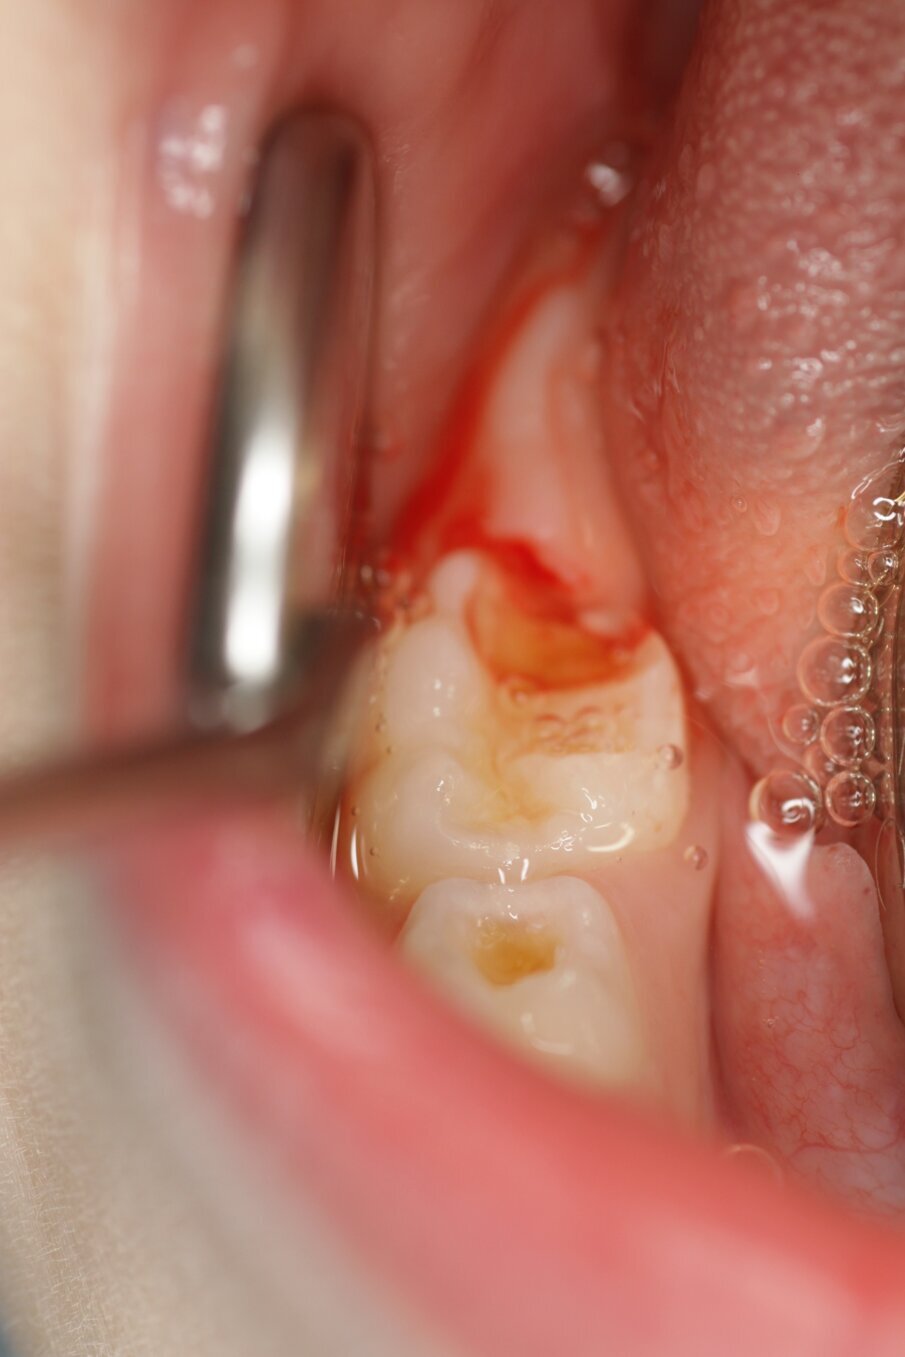

Er wordt bij periodiek mondonderzoek weinig plaque aangetroffen. Sommige laesies zijn inactief en andere worden of blijven actief (afbeelding 3a-c). De 75 werd na een half jaar van een Atraumatic Restorative Treatment (ART)-restauratie voorzien wegens gevoeligheid. Na 2 jaar trad ’s nachts pijn op aan de 64, maar deze verdween weer. Achteraf was het beter geweest als de 64 ook met ART was gerestaureerd (afbeelding 4a-b). Moeder is tevreden over de behandeling na 4 jaar, maar wij zullen nog beter ons best doen om meer zicht te krijgen op de mondverzorging thuis en daar de behandeling op afstemmen. Hoe dan ook, een narcosebehandeling is deze jonge patiënte gelukkig bespaard gebleven.

Afbeelding 3a. Cariëslaesies onderkaak rechts.

Afbeelding 3b. Cariëslaesies ruim half jaar later stabiel.

Afbeelding 3c. Cariëslaesie 64 na een half jaar nog actief.